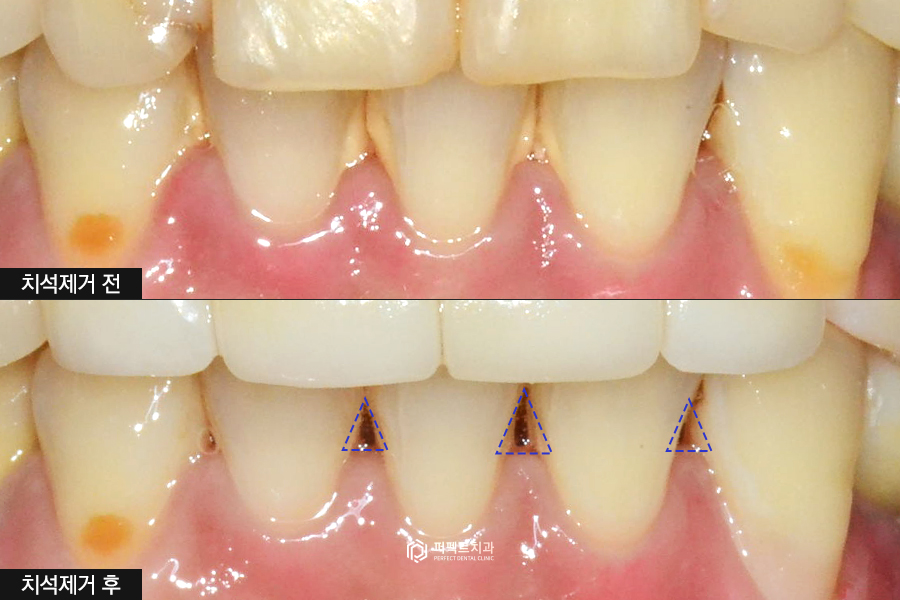

초진사진

처음 내원하셨을 때 사진을 보시면 레진으로 때웠던 부분이 시간이 지나면서 변색이 되어 얼룩덜룩 해진 것을 볼 수 있습니다. 레진으로 넓은 부분을 때우게 되면 몇 개월만 지나도 변색이 생길 수 있어 사진으로 보시는 것처럼 깔끔하지 못하게 보일 수 있습니다.

레진으로 인한 변색 뿐만아니라 치아 사이사이 마모되어 있는 부분들과 아랫니 사이 치석이 있는 것을 확인할 수 있습니다.

그리고 앞니 치아형태를 확인해보시면 앞서 말씀드린 것처럼 밑으로 내려오면서 퍼지는 삼각형 모양의 치아인 것을 확인할 수 있습니다. 이런 부분을 가지런하게 일자로 내려오는 형태로 바꾸길 원하셨습니다.

아래 치아의 경우 치석에 가려져서 빈 공간이 보이지 않지만 치석을 제거하게 되면 블랙트라이앵글이라고 하는 빈 공간이 많이 보이는 상황이었고, 아래 치아에도 마모되고 닳아진 치아가 있었기 때문에 위 아래를 함께 폴리네이트로 진행하게 되었습니다.